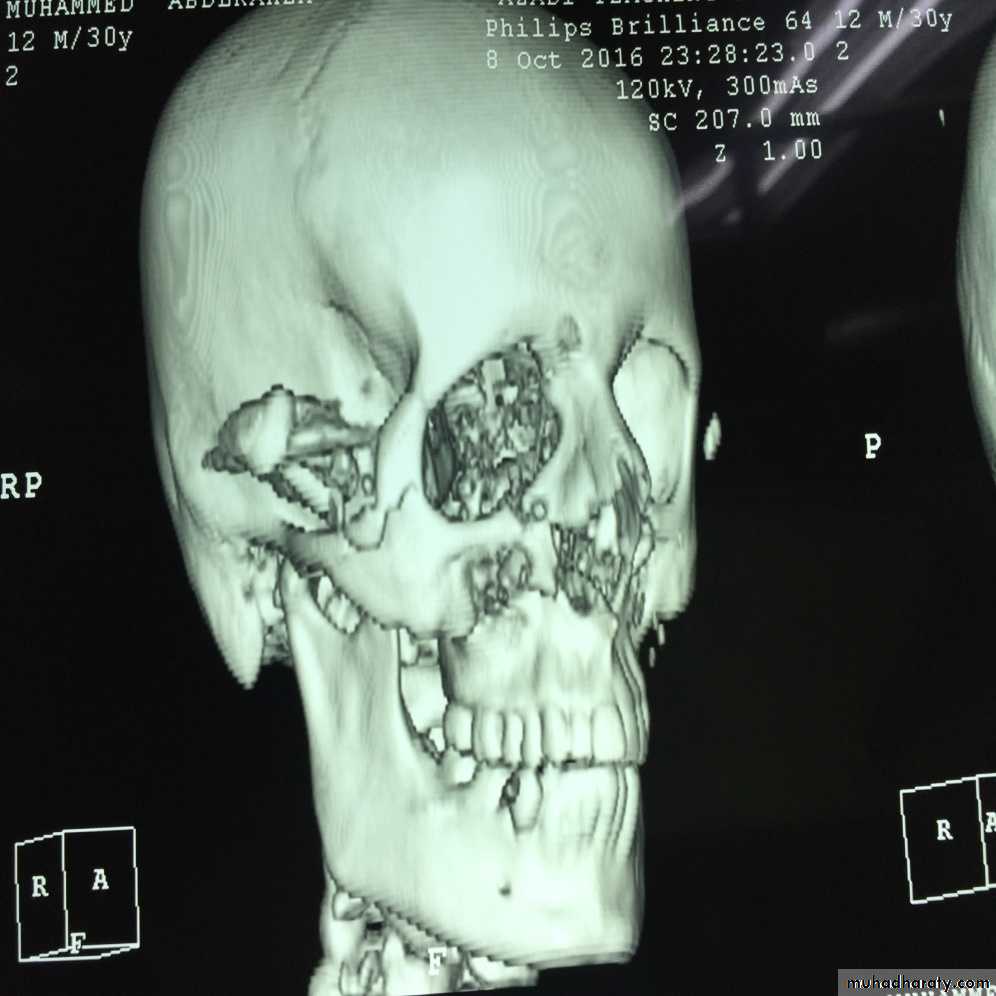

Clinical significance:

• Trigeminal neuralgia.• Blood supply of the face (for plastic surgery)

• Facial paralysis.

• Cavernous sinus thrombosis